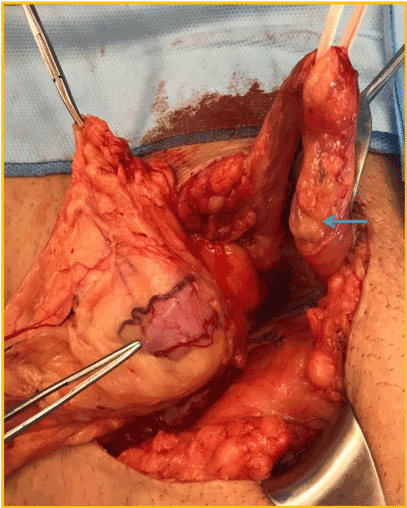

It was mandatory to repair the hernia due to patient discomfort, despite debatable renal function improvement that a surgical procedure could bring to this patient. By using previous Gibson incision the spermatic funiculi and herniary sac were separated (Figure 5). The hernia contained part of the graft´s ureter inside (Figure 6), with a moderate dilation of its proximal segment. A partial ureterectomy, followed by Lich-Gregoir re-implant was performed. No tailoring was needed in this case. The posterior wall was also repaired using the Lichtenstein technique.

Figure 6. Tip of tweezer: ureter inside the herniary sac; blue arrow: spermatic funiculi